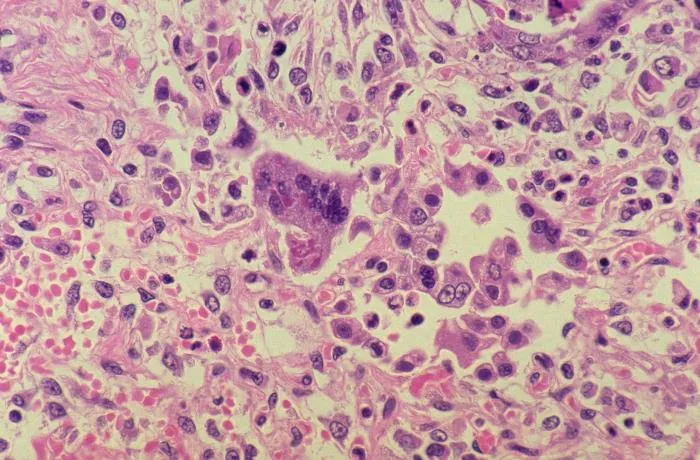

Stara plaga - Odra może powrócić. Preparat przedstawia Morbillivirus

Nowa (stara) plaga

Dziewięciomiesięczny pacjent przywieziony przez matkę do POZ. Z objawami nieżytu nosa gardła i krtani, czemu towarzyszył szczekający kaszel i gorączka (>39 st. C). Dodatkowo z relacji rodzica wynika, że od paru dni dziecko jest jakieś „inne”. Lekarz POZ po zbadaniu pacjenta zdecydował się o włączeniu antybiotyku i ibuprofenu. Matka zastosowała zalecenia, ale po dwóch dniach